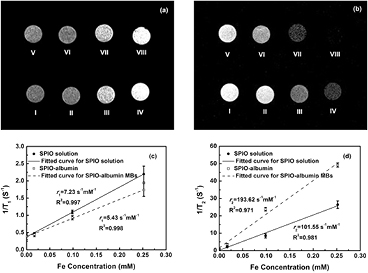

Standard image High-resolution image3.4. In vitro MRI assessments

It is well known that SPIOs can be used as effective MRI contrast agents. Thus, the magnetic responses of SPIO-albumin MBs were assessed firstly to evaluate their potentiality as a contrast agent for MRI. T1- and T2-weighted MR images were captured for MB samples with varied SPIO concentration. Typical T1- and T2-weighted images measured for SPIO-albumin MBs and SPIO solutions are illustrated in figures 5(a) and 5(b), respectively. With the increasing Fe concentration, the T2-weighted images obviously turn darker for both SPIO-albumin MBs and SPIOs (figure 5(b)), while only moderate contrast change can be observed in T1-weighted images (figure 5(a)), which suggests that the tested MBs might be more favorable for the contrast enhancement in T2-weighted MRI due to the integration with SPIOs. The longitudinal and transverse relaxation rates (i.e. 1/T1 and 1/T2) are plotted as a function of Fe concentration in figures 5(c) and 5(d). The slope of linear regression fit gives the longitudinal and transverse relaxivities (i.e. r1 and r2) for the tested sample. The ratio r2/r1 determines whether a contrast agent is most suitable for enhancing MR contrast in T1- or T2-weighted image (Tromsdorf et al 2009, Kim et al 2011). According to the results shown in figures 5(d) and 5(c), the r2 and the r2/r1 ratio calculated for the SPIO-albumin MBs are 193.62 S−1 mM−1 and 35.66, respectively, which are significantly enhanced compared to those of SPIOs (about 2 and 2.5 times, respectively). The enhancement of r2 value might be attributed to the synergetic magnetism effect arising from the aggregation and stabilization of multiple SPIOs in MB shells (Berret et al 2006). The higher measured r2/r1 ratio suggests the current SPIO-albumin MBs may be superior negative MRI contrast agents beyond regular SPIOs.

Figure 5. In vitro T1- (a) and T2-weighted (b) MR images for SPIO solutions and SPIO-albumin MB samples with varied Fe concentrations. (I) Degassed water; (II) SPIOs with 0.01688 mM Fe concentration; (III) SPIOs with 0.0985 mM Fe concentration; (IV) SPIOs with 0.252 mM Fe concentration; (V) albumin-shell MBs with 0 mM Fe concentration; (VI) SPIO-albumin MBs with 0.01688 mM Fe concentration; (VII) SPIO-albumin MBs with 0.0985 mM Fe concentration and (VIII) SPIO-albumin MBs with 0.252 mM Fe concentration. Plots of T1-1 (c) and T2-1 (d) versus Fe concentrations for SPIO-albumin MBs and SPIOs. Figures 5(c) and (d) plot the results for five replicated measurements.

The MRI (figure 5) and US imaging (figure 6) studies have confirmed that, with facile surface modification, the presence of Fe3O4 in MB shell provides enough acoustic and magnetic susceptibility to albumin-shelled UCA MBs to accomplish superb US and MR detectability and sensitivity. To target at multifunctional imaging and drug delivery agents, the therapeutic capability of SPIO-albumin MBs on VEGF165 transfection was also examined in the present work. PEI:VEGF165 complexes were used in this work instead of naked DNA because PEI has been shown to be a relatively efficient non-viral vector and because the synergistic effect of US and PEI on DNA transfection has also been reported in previous work (Deshpande and Prausnitz 2007, Qiu et al 2010, Zhang et al 2013). As reported, US-induced IC activities, which could be dramatically enhanced by the addition of UCA MBs, can transiently enhance cell membrane permeability through sonoporation processes to facilitate the entry of foreign gene/drugs into cells. In order to achieve a better understanding of the mechanisms involved in SPIO-albumin- MB-medicated VEGF165 transfection induced by US exposures, the 'amount' of IC energy cumulated over the US exposure duration (i.e. ICD), cell viability after treatments and effective VEGF165 transfection efficiency were all systemically assessed here at varied p- and SPIO concentration in MB solutions.